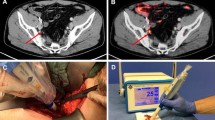

The sterilizable DROP-IN set-up (see Fig. 1) consists of four main parts: (1) a β particle detector, (2) a DROP-IN housing, (3) an electronic processing and read-out unit, and (4) a dedicated statistical software algorithm for signal interpretation.

The DROP-IN housing hosting the crystal and the SiPM was designed to be picked up with the robotic steerable instruments (e.g., ProGrasp Forceps, Intuitive). The DROP-IN shape and diameter (11 mm) were sized to make it compatible with typical trocar dimensions (maximum 12–15 mm). Length (45 mm) and weight (6 g) were optimized to also facilitate maneuverability.

The housing was realized in PEEK (polyetheretherketone): a light, water-tight, sterilizable, robust, and biocompatible plastic material. To meet the required light tightness, black PEEK was chosen. The housing lateral wall thickness was 1.5 mm, while β-detection sensitivity at the front of the detector was maximized by machining the PEEK wall to be as thin as 300 µm.

Since the definition of the most optimal statistical algorithm to guide surgical decision-making was, as already described, one of the aims of this study, no further visual information was shown to the surgeon during the operation, apart from a strip chart of the acquired countings (see Fig. 1).

Before every procedure, the medical grade DROP-IN β probe was sterilized with a standard gas-plasma sterilization cycle. During the surgical procedures, it was used through a standard 12-mm assistant trocar (see Fig. 3). Pick-up of the DROP-IN β probe was simple using the standard da Vinci tools (e.g., ProGrasp Forceps instrument). The surgeon was able to use the probe to scan the field autonomously exploiting all 6 available degrees of freedom, without the need of any help from the assistant. In each patient, the DROP-IN probe was used to perform lymph node examination for around 20 min in total, having therefore reduced impact on surgery duration. No complications related to the use of the prototype probe nor of the [68Ga]Ga-PSMA tracer were observed, and no issues were encountered in the sterilization procedure.

A Operating room during one of the procedures: the black cable coming from the drop-in probe can be distinguished. B MIP image of 68 Ga-PSMA-PET of one of the considered patients (Pt. #3). C View of the da Vinci monitor as seen by the surgeon during the procedure (Pt. #5), including the TilePro split-screen option to view the probe measurements directly in the surgical console